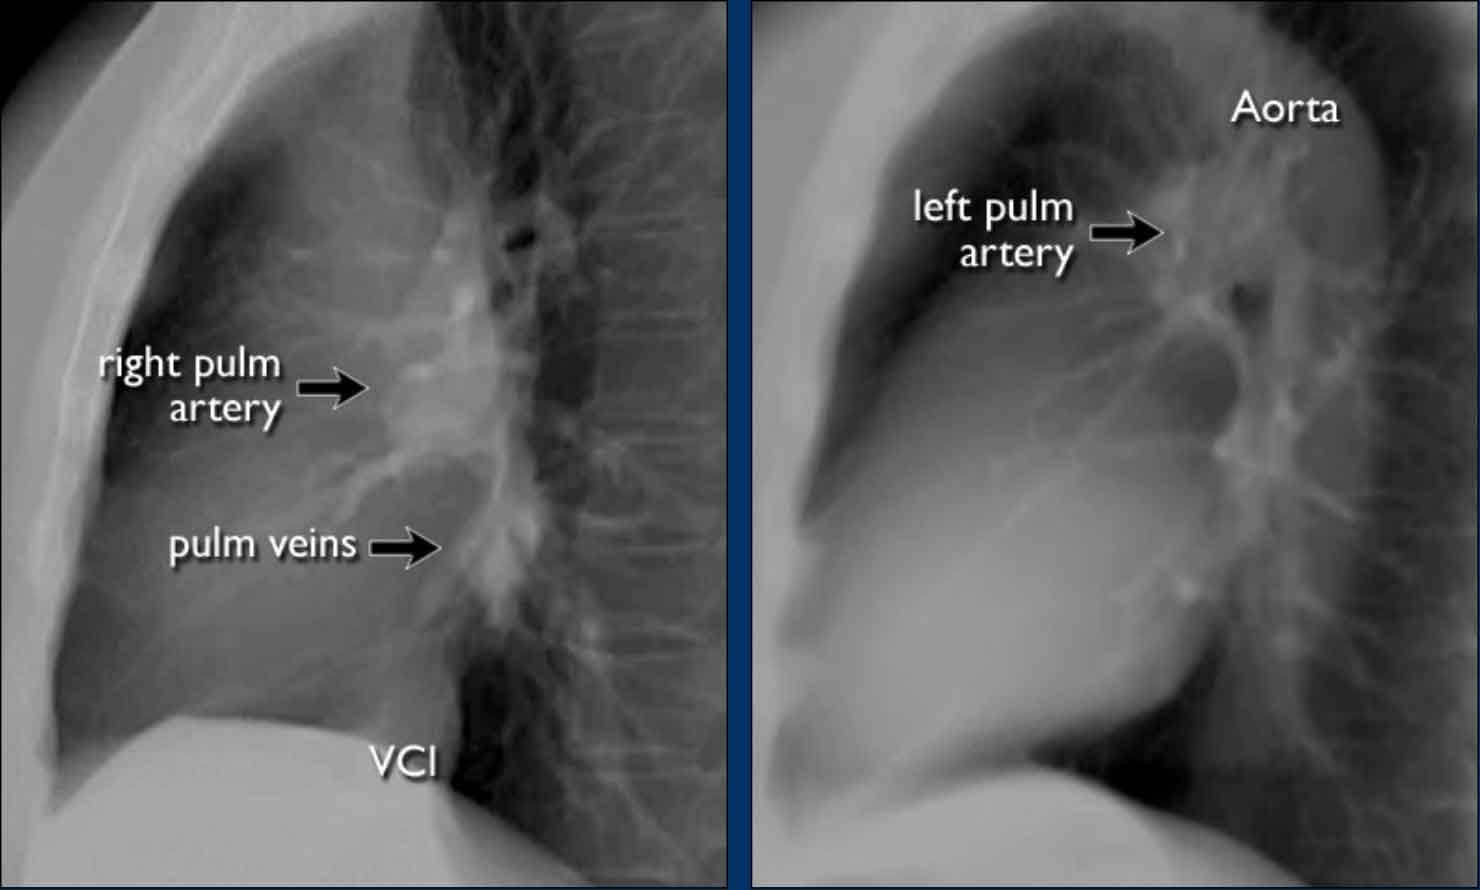

Pulmonary Vasculature and Hilar Structures

The left pulmonary artery (shown in purple) arches above the left main bronchus and is situated higher than the right pulmonary artery (in blue), which courses anterior to the right main bronchus.

Understanding normal hilar anatomy on the lateral view facilitates detection of abnormalities.

For example:

• On the PA view, hilar enlargement may be noted, but it can be difficult to differentiate between vascular dilatation and lymphadenopathy.

• On the lateral view, the presence of rounded opacities in regions where pulmonary vessels are not normally seen strongly suggests enlarged lymph nodes.

In this case, the patient was diagnosed with sarcoidosis.

Additionally, note the widened paratracheal stripe, another indicator of mediastinal lymphadenopathy.

Hili

The normal hilar shadow on chest radiography is predominantly vascular in nature—comprising approximately 99% of pulmonary arteries and, to a lesser extent, pulmonary veins (1).

These vascular structures have well-defined, smooth margins and demonstrate normal branching patterns.

An important anatomical consideration is that the left hilum is normally situated higher than the right.

This relationship arises from the course of the pulmonary arteries: the left pulmonary artery arches over the left main bronchus, while the right pulmonary artery courses anterior to the right main bronchus, which is typically positioned lower than its left counterpart.

In a minority of cases, the hila may be at the same level, but the right hilum should never be higher than the left.

These arteries have a more vertical orientation compared to the pulmonary veins, which run more horizontally toward the left atrium, located inferior to the level of the main pulmonary arteries.

On lateral chest radiographs, both pulmonary arteries and veins are identifiable and should not be misinterpreted as lymphadenopathy. Occasionally, pulmonary veins may appear prominent.

The left main pulmonary artery passes superior to the left main bronchus and lies higher than the right pulmonary artery, which courses anterior to the right main bronchus.

The included images are thick-slab sagittal CT reconstructions of the thorax, which enhance visualization of hilar structures.

The lower lobe pulmonary arteries descend from the hilum in a vertically oriented fashion.

Radiographically, these vessels are colloquially referred to as the “little finger” due to their size and shape, approximating that of a little finger (1).

On PA chest radiographs, the "little finger" of the right lower lobe pulmonary artery is visible in approximately 94% of normal individuals, while on the left side it is visible in about 62% (1).